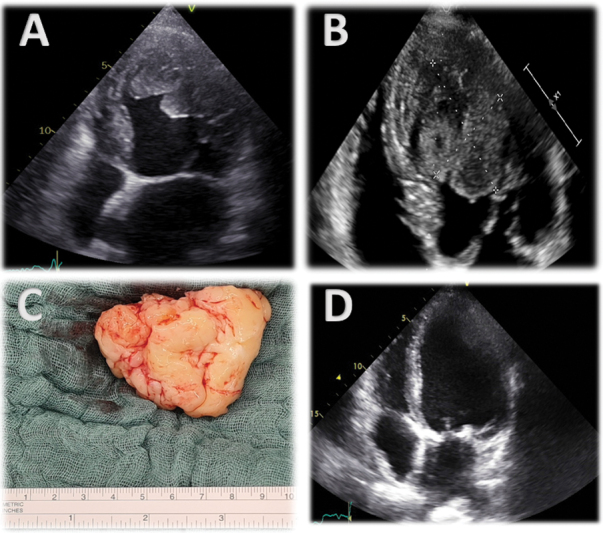

A 71-year-old man with dilated cardiomyopathy without clinical complaints revealed a suspicious finding in checkup. After a multimodality cardiac imaging, the suspicion of a malignant primary cardiac tumor in the left ventricle was substantiated and the patient underwent minimally-invasive cardiac surgery for tumor resection. Postoperative chemotherapy with multiple cycles of liposomal doxorubicin was established and supported by proton beam radiotherapy. Two-year follow-up revealed no disease recurrence.

Abstract Image